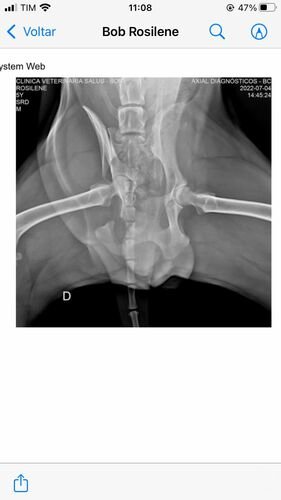

Bom, o Bob está com o quadril extremamente fraturado (conforme laudo disponível), inclusive o quadril dele está virado para o lado, ele precisa realizar um procedimento cirúrgico complexo e vai precisar utilizar placa (conforme foto do orçamento cirúrgico). Todos os custos de consulta e medicação eu consegui custear até agora (comprovantes disponíveis) mas infelizmente eu não consigo custear o valor da cirurgia em tão pouco tempo e peço ajuda de todos, todo valor é extremamente bem-vindo. Me ajudem a salvar a vida do Bob!

Laudo e Raio-x: